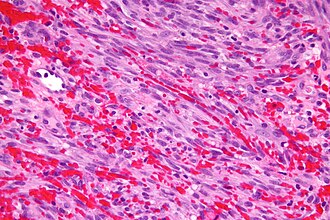

Kaposi sarcoma. H&E stain. | |

| LM | vascular lesion (abundant RBCs), +/-"promontory sign", +/-spindle cells with minimal nuclear atypia, RBC extravasation, +/-intracytoplasmic hyaline globules, +/-hemosiderin deposits, +/-plasma cells |

Features:[7]

- Vascular lesion (abundant RBCs) with:

- +/-"Promontory sign" - small vessel protruding into an abnormal vascular space.[8]

- Not pathognomonic for KS.[9]

- +/-Spindle cells with minimal nuclear atypia.

- RBC extravasation - very useful - important feature.[10]

- +/-Intracytoplasmic hyaline globules - uncommon - one usu. needs to search for 'em.[11]

- Pale pink globs (that are paler than RBCs) - important feature.

- +/-Hemosiderin deposits.

- +/-Plasma cells.[12]